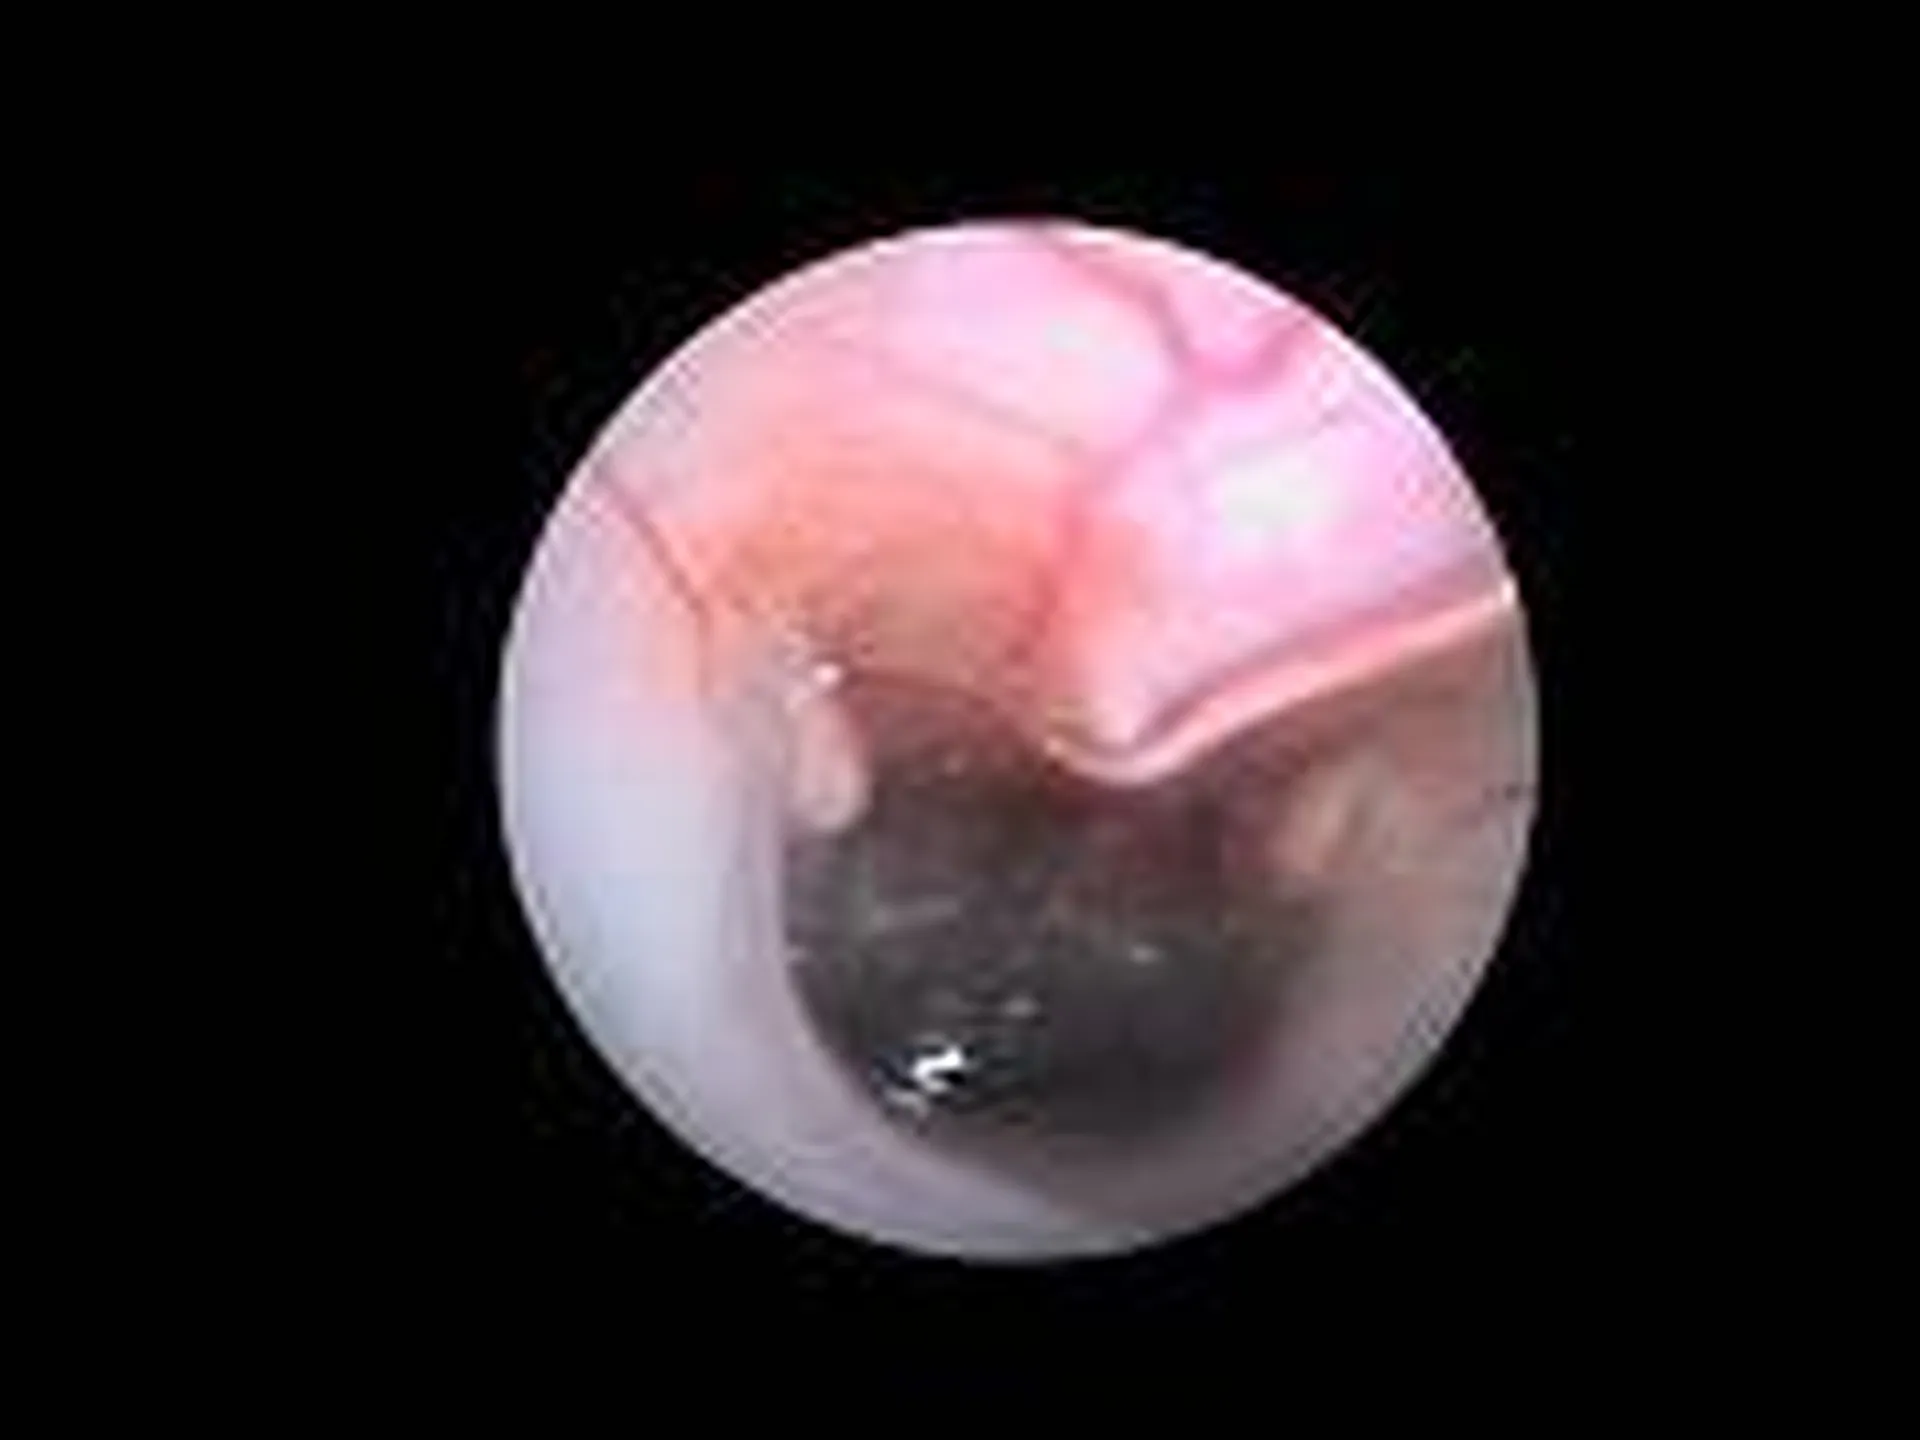

Affection touchant les narines (on parle de rhinoscopie) : retrait de corps étrangers, visualisation de processus cancéreux, infections nasales bactérienne ou fongique

Affections touchant l’arbre respiratoire (endoscopie respiratoire) : corps étranger (épillet), paralysie laryngée collapsus trachéal, infection respiratoire bactérienne, fongique (aspergillose), parasitaire (angiostrongylose), tumeur.

Des clichés sont effectués tout au long de l’intervention afin que vous puissiez visualiser les affections notées au cours de l’examen.